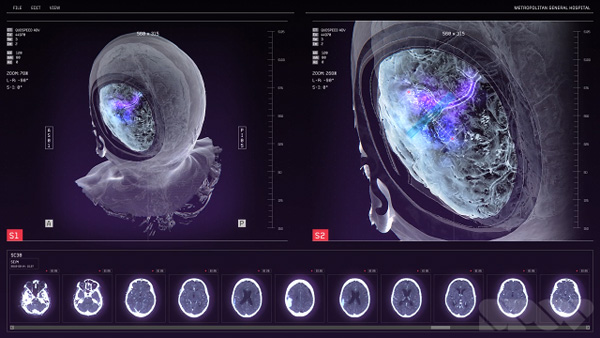

The art department also supplied them with a lot of the reference they needed for looks – ultrasound output, X-ray images and MRI scans. SPOV sourced some PACS screens as well, as samples of the standard Picture Archiving and Communication System that medical staff use to compile databases of all kinds of data.

Achieving the authenticity required in their brief meant following through on all details in a genuine way, so that everything fit in and would satisfy the fans and geeks. The small details, colours, textures, views and bits of text aren’t added gratuitously for effect, but appear as they would on real imagery for screens in a hospital. “Actually, we had a secret advantage in that our former studio manager at that time was preparing to be a nurse. She would look over our work and tell us what looked out of place or was missing – just what we needed to help sell the images,” said Allen

Nevertheless, instead of looking creepy or frightening, the results are strangely beautiful and pull the viewer toward the inner world of brains, bones and blood vessels. This look is no accident. SPOV’s main pipeline is based on Cinema 4D used together with After Effects for compositing – tools SPOV has used for years on nearly all projects and which nearly all of their artists are very familiar with.

Allen said, “For some of the artists here, Cinema 4D plus Creative Cloud software, mainly After Effects, sometimes Photoshop, are the means to create nearly anything. Over time, some have developed skills in 3D software like Maya, or ZBrush as a dedicated sculpting tool. But on ‘Doctor Strange’, although we needed diverse 3D effects, textures and modelling, only Cinema 4D and After Effects were used for everything, including a huge amount of detailed sculpting on some of the assets. We also successfully pushed Cinema’s Proximal Shader to create a smooth, adjustable ghosted effect.

“We could use soft, controllable Boolean operations for the ghosting of hard surfaces. In addition we could render out and animate a black-and-white map precisely determining the cut away areas. Passes were rendered and exported from Cinema 4D, and then layered up in After Effects for compositing.” A nice example of how this looks in the film is in the images above and at the top of this article, showing a portion of the skull cut away to reveal the brain inside.